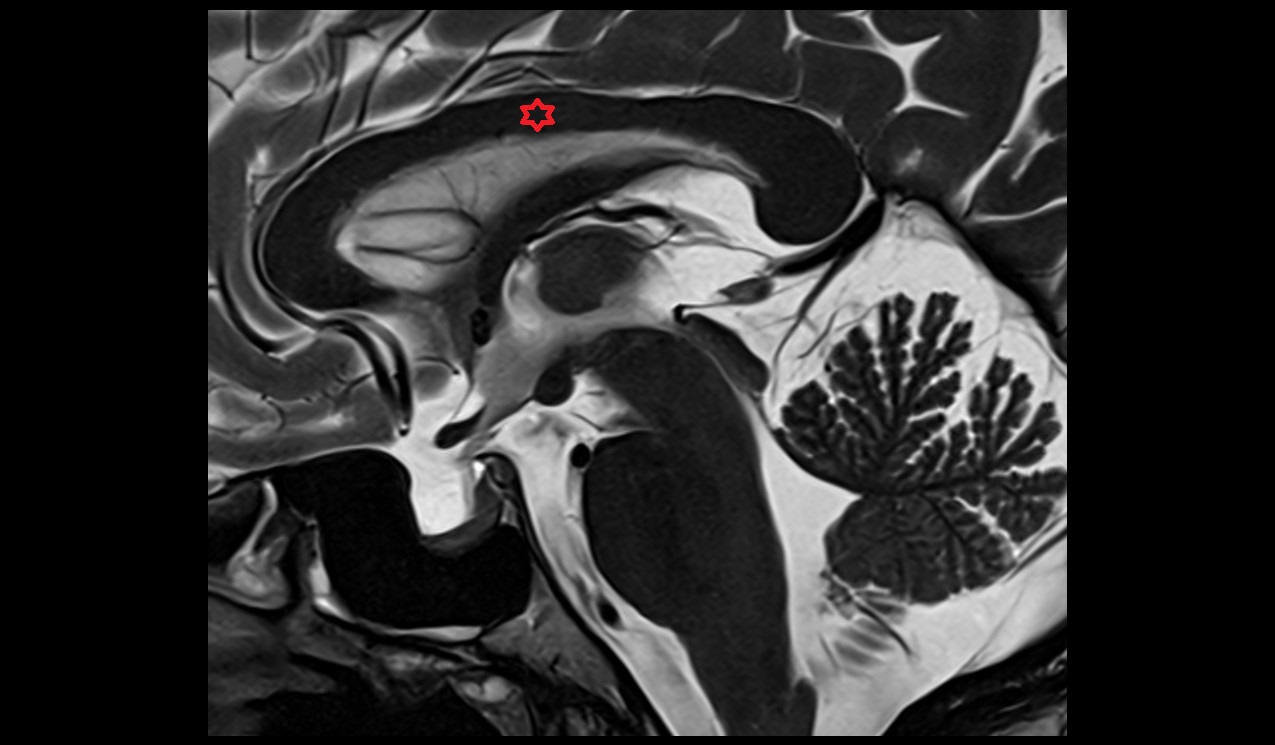

- Aqueduct of midbrain (Sylvian Aqueduct)

- Cerebral aqueduct